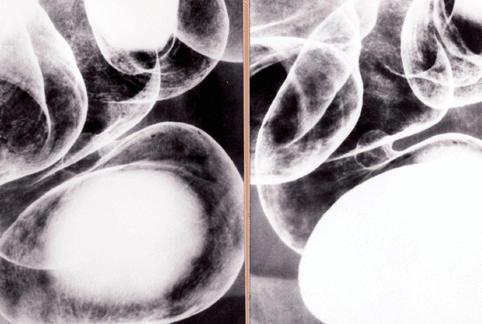

疾患(病理主体)の分類悪性上皮性腫瘍/腺癌

部位(臓器別)大腸/直腸

検査方法X-P

腫瘍の肉眼分類0型(表在型)/IIa型(IIa)

病変の最大径(ミリ)10〜14

腫瘍の深達度sm